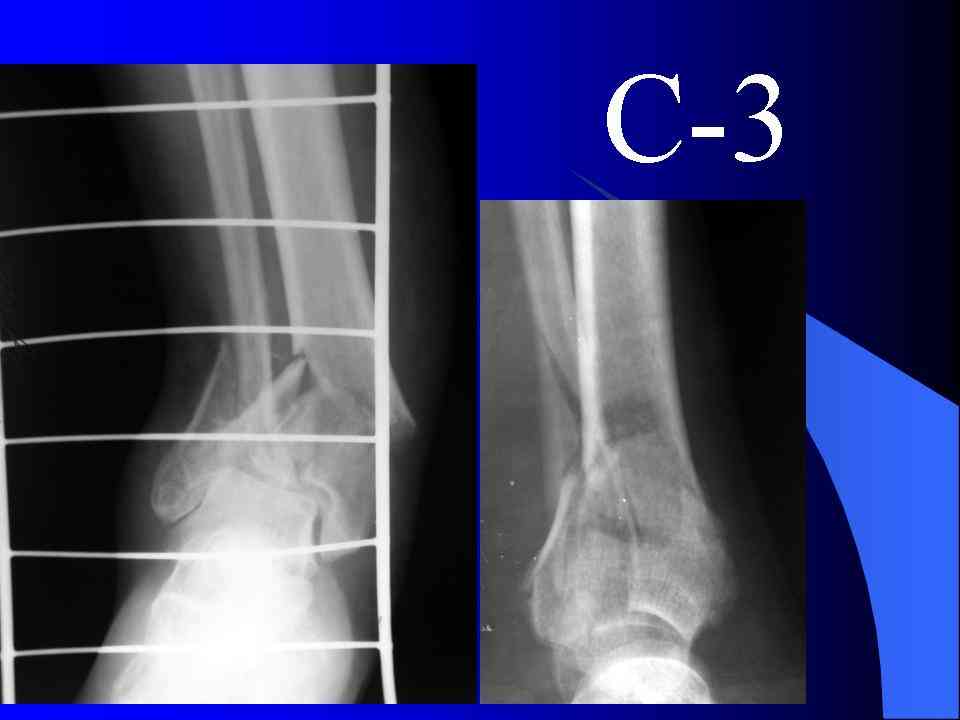

Посылаю результат лечения предыдущего больного через год.

На рентгенограммах типичный перелом пилона по типу С-3. есть опыт до 100 открытых опреаций у нас в клинике. 20 примерно в год. Принцип один -все внутрисуставные переломы нуждаются в открытой репозиции и внутренней стабильной фиксации. При поступлении КТ не надо, так как получается только нагромождение костей. Истинной картины нет. Главное восстановить длину малоберцовой кости - это ключ к успеху. При поступлении меньше всего надо думать о сосудистых расстройствах, т.к. сама операция и репозиция даже сначала частичная даёт улучшение сосудитых нарушений. Причём очень быстро. Операция в 2этапа. При поступлении доступ позади наружной лодыжки, причём обязательно. После этого репозиция малоберцовой кости и фиксация пластиной 1/3 трубки под винт 3,5. Дренаж и любой аппарат наружной фиксации. Затем после спадения отёка на 5-7-10 день аппрат снимается и дугообразный разрез спереди от медиальной лодыжки 10-12 см. Главной чтобы расстояние между 1 и вторым разрезом было не меньше 7-8 см. Тогда не будет некрозов лоскутов. Таранная кость используется как матрица на неё укладываются отломки и фиксируются пицами. Ренг-контроль. Отломки лежат все отдельно, но ничего не высыпется. При переломах С-3 всегда нужна костная пластика (из крыла). Фиксация пластиной лист клевера простой или LCP. Гипс не нужен. Дренаж до 48 часов. Операция длится 3-4 часа обязательно без жгута. Посылаю примерно такой же случай.